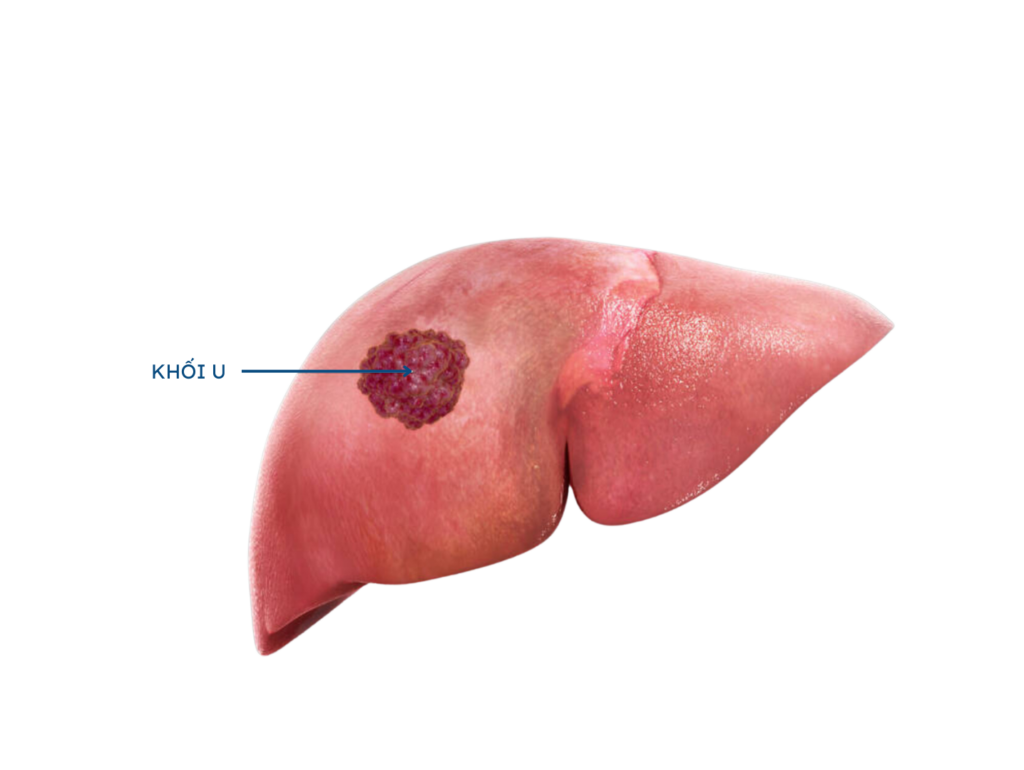

Nhiễm virus viêm gan B mạn (HBV), viêm gan B và viêm gan C (HCV) là yếu tố hàng đầu gây ung thư gan

Xét nghiệm AFP giúp phát hiện dấu hiệu của khối u gan